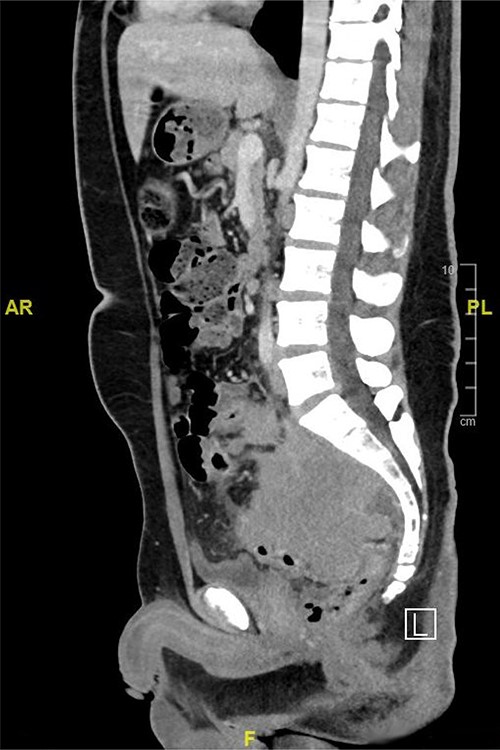

Computed tomography (CT) scan of the abdomen showed a large upper and mid-rectal mass (Fig. 1). Colonoscopy was done and it revealed a polypoidal mass located 3 cm from the anal verge and extending up to 15 cm from anal verge. The mass was erythematous, and friable.

CT scan of the abdomen showed a large upper and mid-rectal mass.